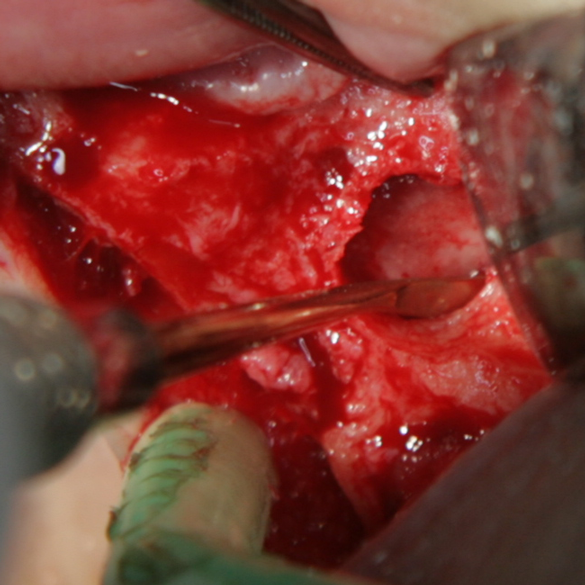

Отворен максиларен синус в началото на интервенцията. Случаят е интересен със следното - твърде атипична форма на трепанационния отвор. На какво се дължи на това - на лошо планиране на оперативния достъп или на нещо друго? Дължи се на факта, че отначало въпросната намеса беше планирана като балонен синуслифт; за съжаление обаче мембраната на синуса се разкъса и надуването на балона стана невъзможно.